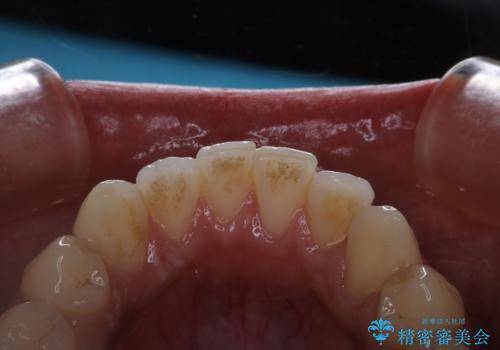

タバコによるヤニ、着色、歯の汚れをPMTC(60分コース)で除去。

タバコのヤニを取って歯を白くしたい